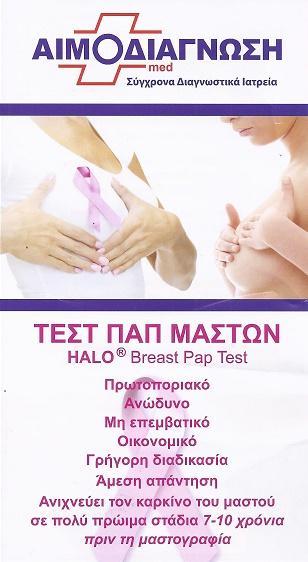

Μικροβιολογικό εργαστήριο Καπανδρίτι, τεστ παπ μαστού, τεστ τροφικής δυσανεξίας Καπανδρίτι